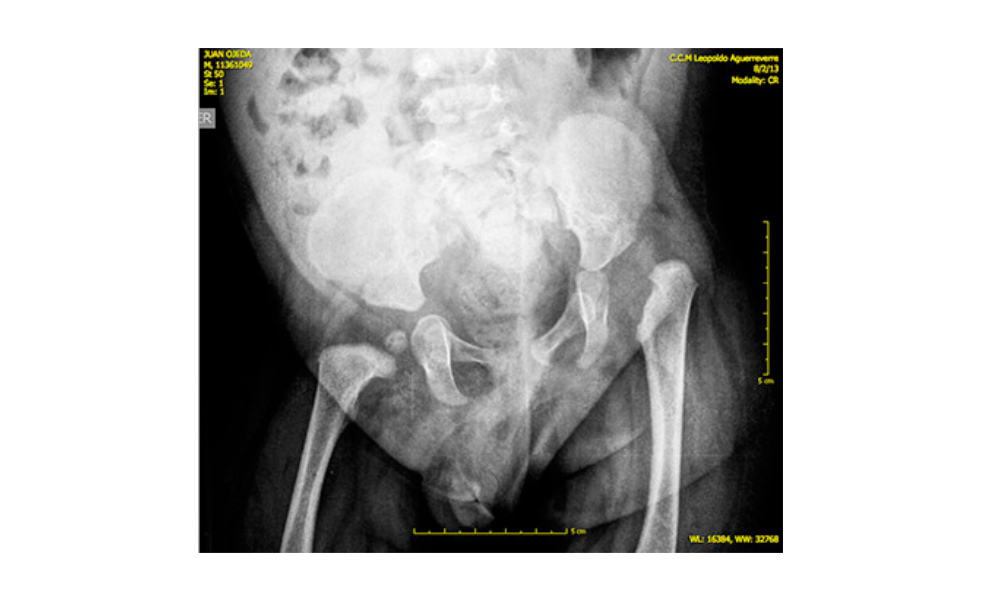

Al superar todas las dificultades inherentes a su nacimiento, me dediqué a un cuidado exclusivo y minucioso, pues eran bebés muy pequeños. Juanchi tenía problemas de reflujo, el momento de comer requería de cuidados extremos para evitar que se ahogara. A escasos dos meses de nacidos fueron evaluados por especialistas de diferentes áreas, y es cuando el pediatra y el neurólogo se dan cuenta que Juan, no sólo presenta su pie izquierdo equino-valgo y su pie derecho en posición talo-valga, sino que carece de sensibilidad en ambos miembros, con ausencia muy significativa de movimientos en los dedos. También se dan cuenta de que presenta asimetría de las articulaciones de las caderas, y lo remiten al médico Ortopedista. Llenos de fe, aceptamos los resultados y nos preparamos para iniciar el proceso de sanación de Juanchi.

En febrero de 2013, Juanchi presentaba una luxación de la cadera izquierda por su afectación neurológica denominada mielodisplasia. Corregir esta luxación era el primer paso. Esta cirugía se llevó a cabo en Septiembre de 2013.

Comenzaron los infinitos exámenes, las distintas visitas a médicos especialistas de columna, de caderas, de miembros inferiores, neurocirujano, entre otros. Hubo disparidad de criterios, pero finalmente se detreminó que Juanchi presenta una grave lesión congénita por mielodisplasia asimétrica de nivel L5-S1 en el hemicuerpo izquierdo y S1-S2 en el hemicuerpo derecho, diagnosticada por el Dr. Miguel Ángel Galbán, médico Venezolano, ortopedista infantil y especialista en reconstrucción de miembros inferiores. Este diagnóstico, aunque no lo esperábamos lo asumimos con temple y Fe de que sería superado por Juanchi con la ayuda y el apoyo de toda su familia.

En septiembre del 2013, llega el primer paso de importancia que marcaría un avance en el cuadro clínico de Juanchi, el Dr. Galbán, decide, iniciar el procedimiento de reconstrucción de los miembros inferiores de Juanchi, realizándole una cirugía donde corrigió la luxación de cadera izquierda mediante la corrección de la displasia (aplanamiento) del acetábulo, corregir la deformidad de la parte proximal del fémur y colocar la cabeza femoral en su lugar correcto, todo esto mediante una técnica novedosa denominada “SUPERHIP”, técnica descrita por el Dr. Dror Paley para deformidades congénitas de la cadera y modificada por el Dr. Galbán para casos como el de Juanchi.